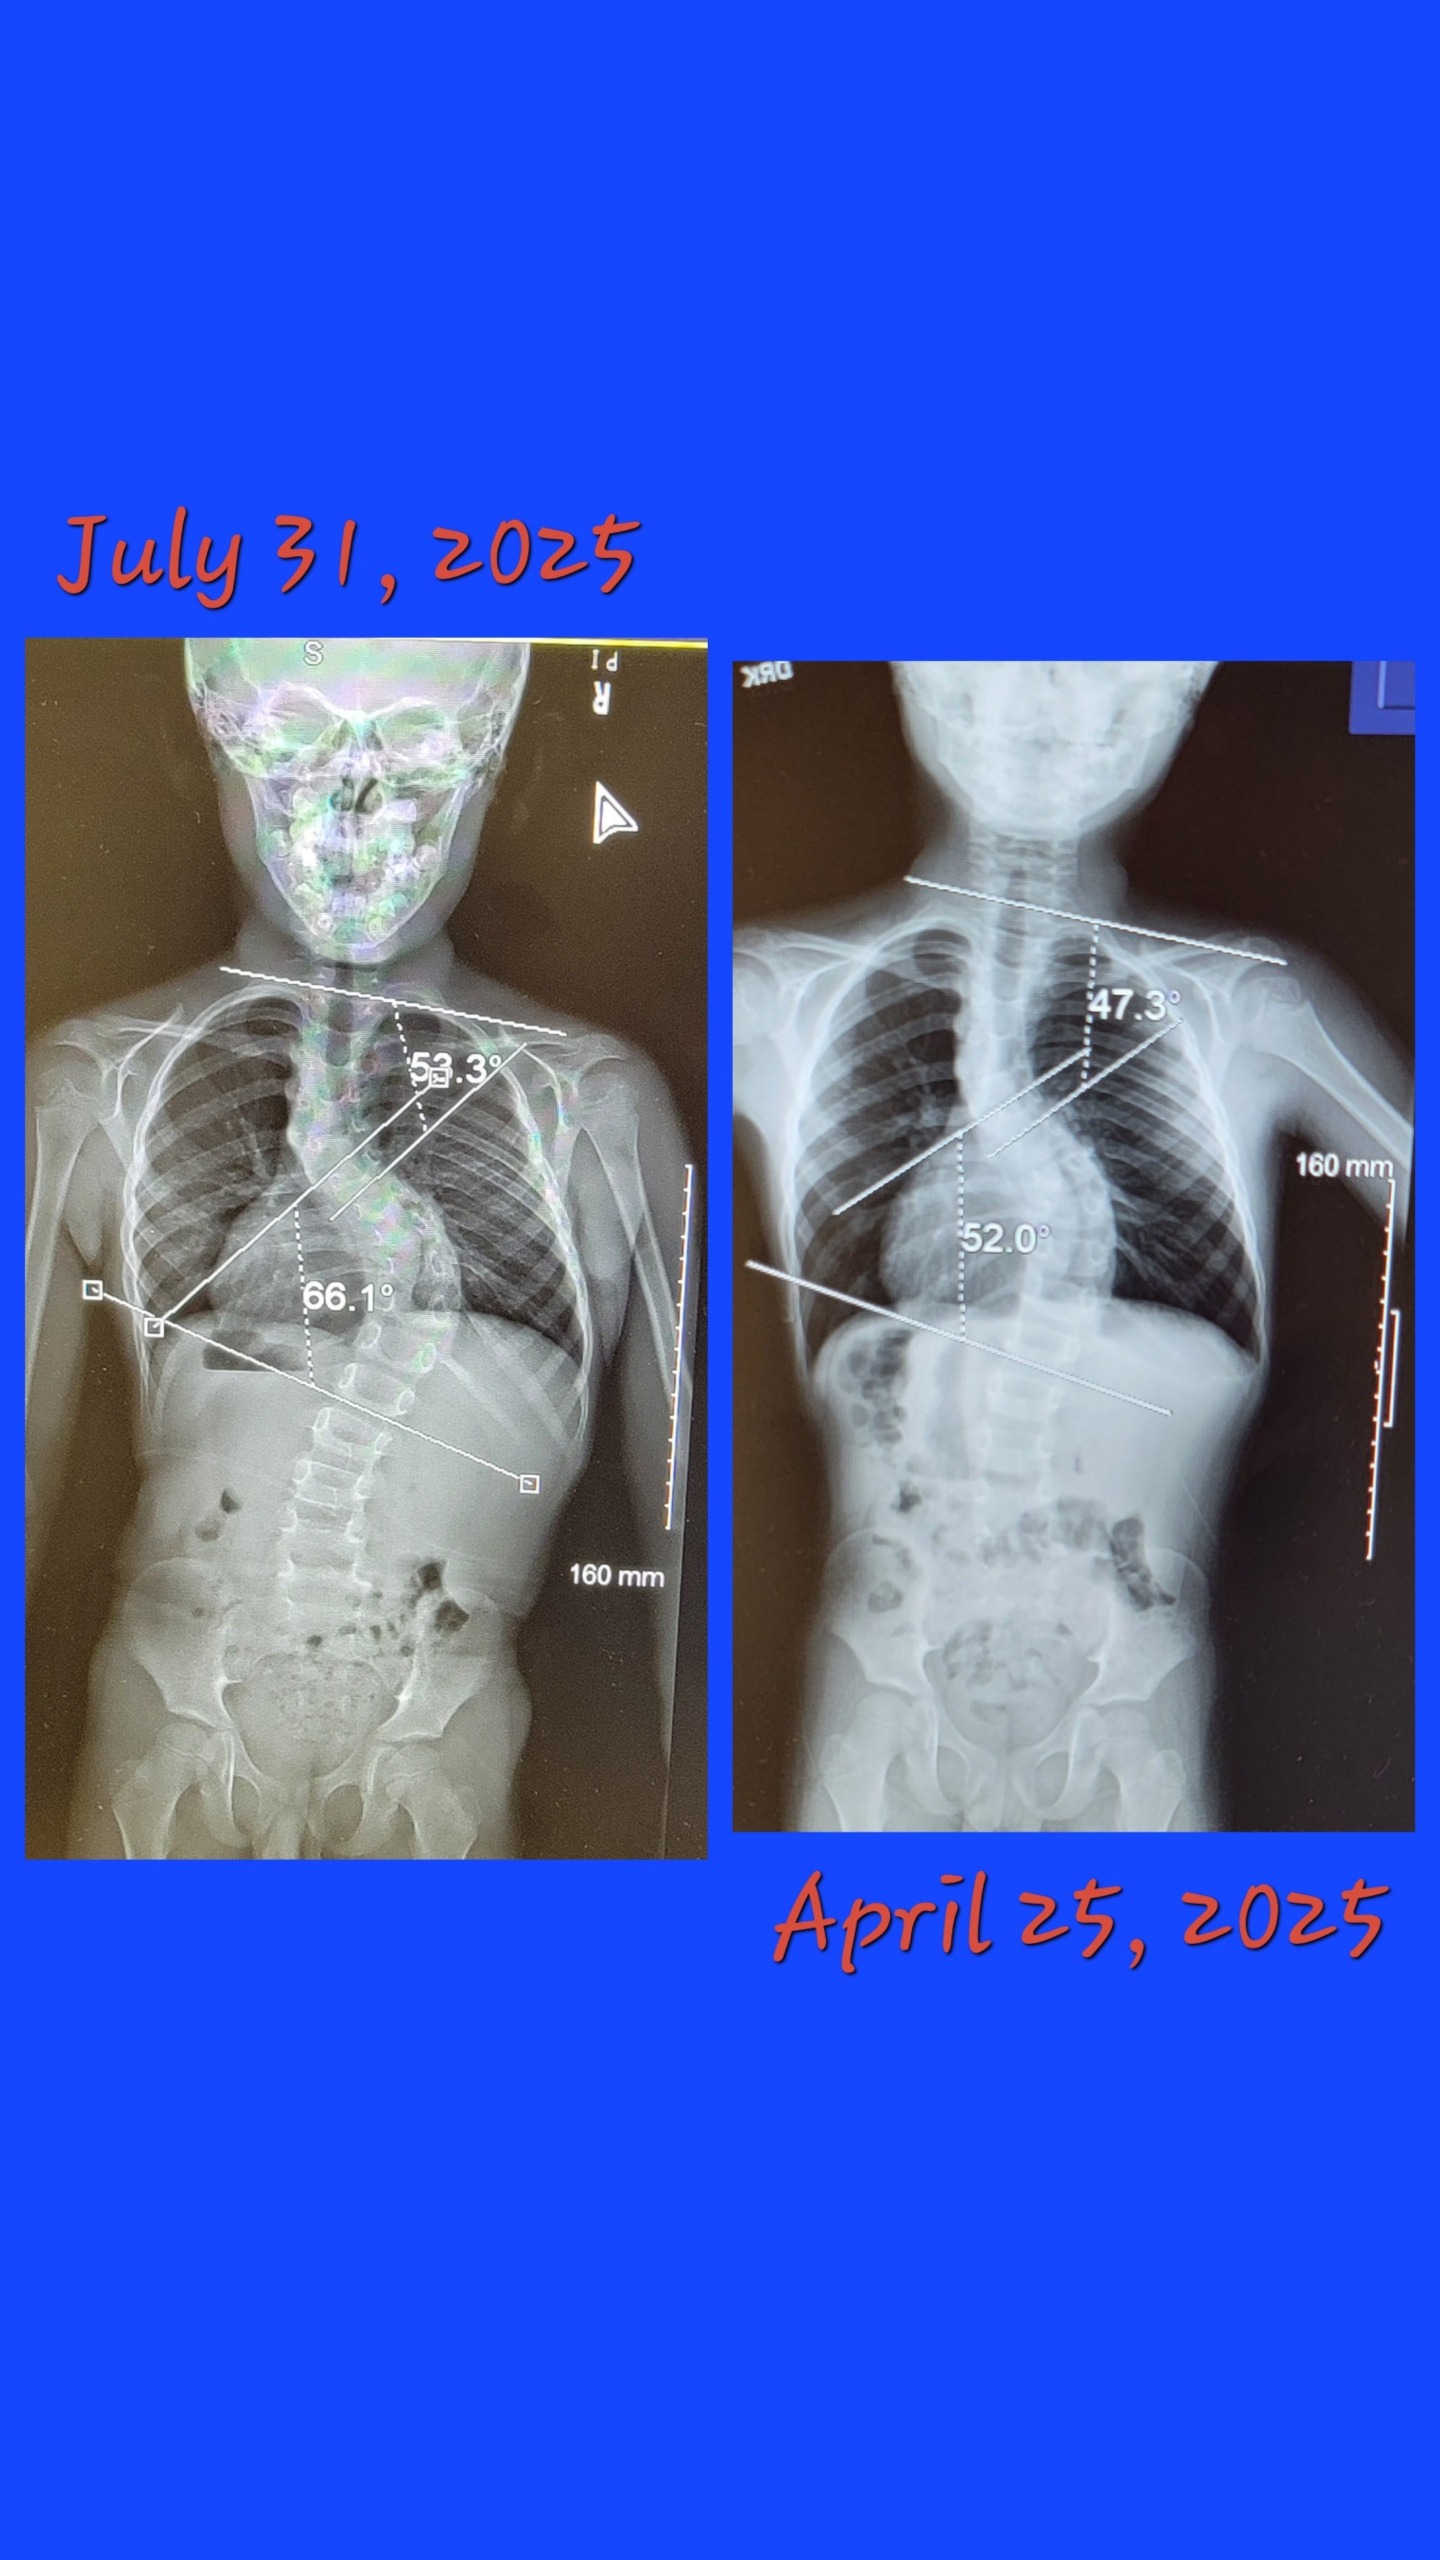

My dear friend, Amanda and her 8-year-old son, Cayden, are in need of some extra help. Cayden is an amazing and very special boy. He was born with severe scoliosis. This is a very painful and debilitating condition for this little guy. His scoliosis has been progressing at an alarming rate every millimeter his little body grows and surgery can no longer wait. He is scheduled to undergo corrective surgery on September 9th, 2025, at Shriner's Children's Hospital in Chicago.

Well, the time is here. Cayden's scoliosis is basically a runaway train. Pre-op is August 21st, and surgery is scheduled for September 9th at the Shriner's Children's Hospital in Chicago.

Our little boy will have spinal rods. The surgeon is hoping to utilize the newer technology of Magec Rods. The determination of newer technology vs. the older style rods will be made once they get in there, and it depends on if there is enough muscle and skin tissue to cover the hardware. Cayden has had a growth spurt but is still a little guy.